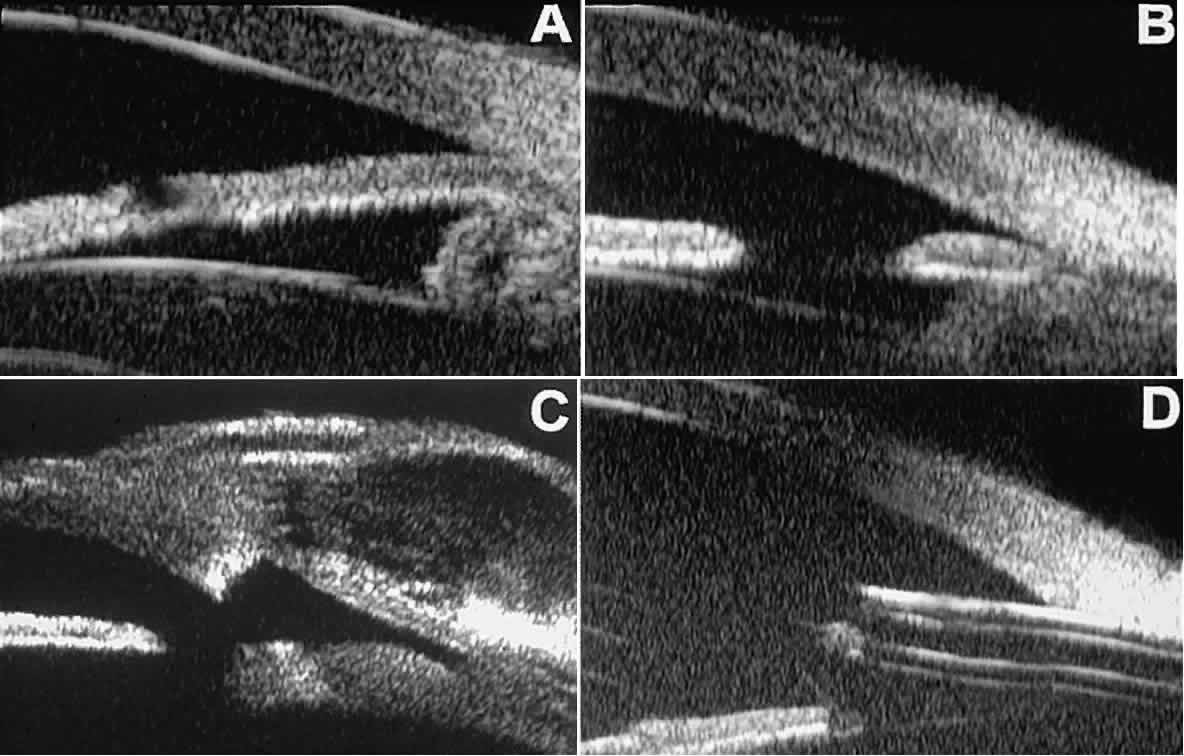

Ultrasound biomicroscopy appears to be helpful postoperatively in determining the extent of postoperative complications of cataract surgery such as serous choroidal detachment (see Fig. 13A), iridocapsular adhesion (Fig. 19A), postoperative hyphema (see Fig. 19B), stripping of Descemet's membrane (see Fig. 19C), and wound gaping (see Fig. 19D).

Fig. 19. Complications of cataract surgery revealed by UBM. A. Capsular adhesion to midzone of iris. B. Postoperative hyphema. Clot appears denser than aqueous with suspended blood cells. C. Stripping of Descemet's membrane. D. Wound gape.

UVEITIS

In eyes with iritis or iridocyclitis, UBM can demonstrate many inflammatory features in detail (Fig. 20).4 Inflammatory cells in the aqueous (see Fig. 20A) can be visualized by UBM as sonoreflective particles floating in the sonolucent aqueous. Keratic precipitates appear on UBM (see Fig. 20B) as sonoreflective cellular clumps adherent to the endothelial surface of the cornea. In hypopyon uveitis (see Fig. 20C), UBM shows the collection of white blood cells to be a dependent sonoreflective mass in the anterior chamber with adherence to the peripheral iris. Inflammatory nodules of the iris (see Fig. 20D) appear as relatively ill-defined, moderately sonoreflective lesions expanding the normal iris stroma or lying superficially on it.

Fig. 20. UBM features of uveitis. A. Inflammatory cells suspended in anterior chamber aqueous. B. Keratic precipitates appear as small sonoreflective bumps on peripheral corneal endothelium. C. Hypopyon. Mass of inflammatory cells fills inferior anterior chamber angle, and dispersed cells are suspended in central anterior chamber aqueous. D. Inflammatory mass of pupillary zone of iris. Mass disappeared after corticosteroid therapy.

TRAUMA

After blunt ocular trauma, UBM can be used to evaluate iris-angle abnormalities associated with and possibly obscured by hyphema, including angle recession and cyclodialysis, and to illustrate the presence and extent of blood clots.4 Angle recession is characterized on UBM (Fig. 21A) by posterior displacement of the point of attachment of the iris to the sclera. In the acute stage, the post-traumatic recess is usually filled with blood. Cyclodialysis (described and illustrated earlier) appears on radial UBM slices through the limbal region (see Fig. 13B) as a fluid-filled cleft between the sclera and ciliary body.13 This abnormality is by definition associated with at least a localized ciliochoroidal effusion.

Fig. 21. UBM features of ocular trauma. A. Angle recession with traumatic hyphema after blunt injury. B. Intracorneal foreign body (rose thorn fragment). Note inflammatory cells in adjacent aqueous. C. Intraocular foreign body (glass fragment in inferior angle).

After ocular perforations, lacerations, and intraocular surgery, UBM can show abnormalities such as retained foreign bodies too small to be imaged by other technologies.3,4 Foreign bodies appear on UBM (Fig. 22A and B) as highly reflective focal lesions that are frequently associated with inflammatory features.

Fig. 22. UBM features of primary neuroepithelial cysts of iris and ciliary body. A. Primary neuroepithelial cyst of iris midzone. B. Primary neuroepithelial cyst of iridociliary sulcus. C. Multiple neuroepithelial cysts of peripheral iris and ciliary body. D. Neuroepithelial cysts of pars plana of ciliary body shown in circumferential slice.